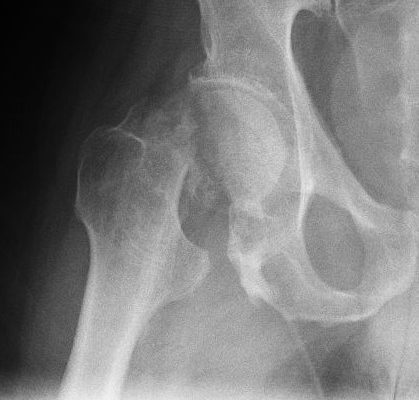

• шейка бедра.

Патологический перелом диагностируется на основании жалоб пациента, осмотра и характера травмы — если к кости было приложено небольшое усилие.

Важны результаты рентгенологического исследования. Компьютерная томография и магнитно-резонансная томография (МРТ) также могут оценить состояние ваших костей и окружающих тканей. Во время этих тестов можно наблюдать изменения, которые делают возможным образование патологического перелома.